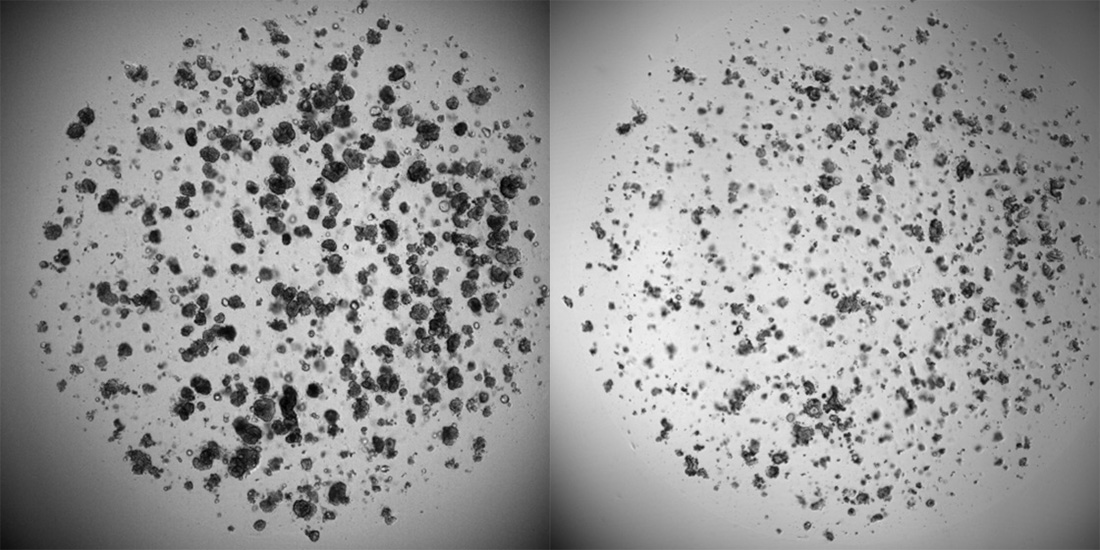

These are mini-tumors grown in the lab, taken from a patient with colorectal cancer. The image was captured using a special technique that combines multiple stains and analyzes the images with AI algorithms. The technique has many applications, such as studying how a drug works or identifying differences between cancer patients who are more or less sensitive to a specific treatment. “The goal is to further develop the technique to detect differences that are significant but that a human would not notice with traditional light microscopy”, says Flobak. The image was taken by postdoctoral researcher Christa Ringers as part of her work at NTNU.

Cancer cells in the laboratory. On the left are cancer cells that have grown for a week without any drugs added. On the right are cancer cells from the same patient after being exposed to chemotherapy. Photo: NTNU